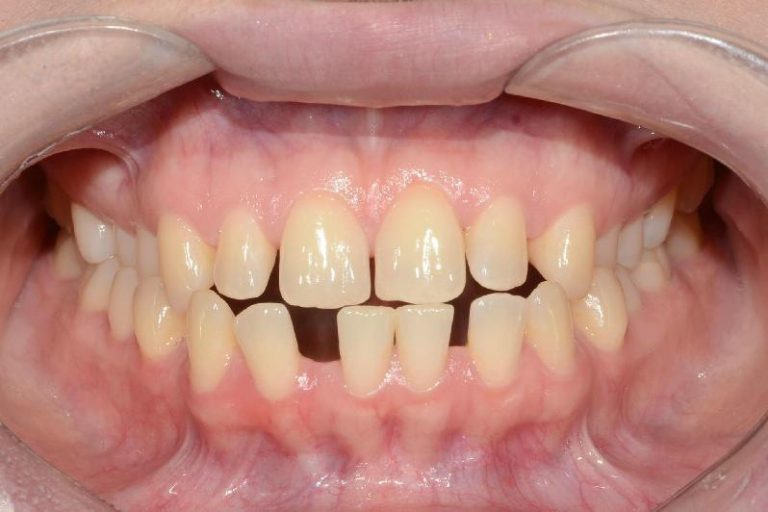

Classe III, articulé croisé antérieur, béance, espacement, diastème

Résultats obtenus

- Relation de classe I obtenue

- Guidage fonctionnel des canines des deux côtés

- Articulé antérieur corrigé

- Forme de l'arcade améliorée

- La ligne de sourire esthétique a été obtenue

- Des arcades harmoniques ont été réalisées

État final